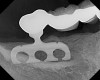

Figure 40 – Radiograph showing significant bone loss around the implant, 1 year after placement.

Figure 40

Dental implants are the best option we have today to replace missing teeth. However, complications during treatment may arise, such as failure to osseointegrate or bone loss while in function (Figure 40).

Figure 42 – Radiograph of a fractured posterior implant.

Figure 42